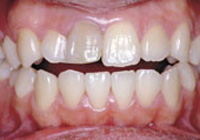

症例1:乱杭歯「歯並びが乱れている」

治療前

治療後